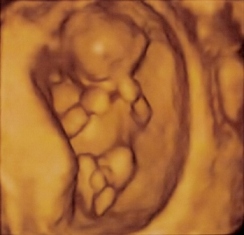

Nekem tegnap csodálatos napom volt! Megvolt a 12. heti ultrahang vizsgálatom és mindent rendben találtak! Gyönyörű már most! Doktornő is említette, hogy nagyon jó húsban van! Nagyon szépen nő és fejlődik! Már 6 cm (többször nézte a CRL-t és 6,1 cm-nek is mérte) és a súlyát 67g-nak becsülte a gép. 3 nappal nagyobb a koránál. A MÁV kórházban is voltam így a nyaki redő vastagságra két értékem van, de mindkettő megfelelő. Az integrált teszt eredménye majd jan. 18-a körül lesz meg, de mindkét doki mondta, hogy nem láttak semmi kórosat. Orrcsont is látható.

Van 3D-s és 4D-s képem is, benne volt az árban és a DVD is a vizsgálatról, így megvan a karácsonyi mozink! A férjem úgy látom most fogta fel, hogy tényleg kisbabánk lesz.

Képet nem merek mutatni, de ha szeretnétek, akkor egy jól sikerült 4D szívesen feltöltök...